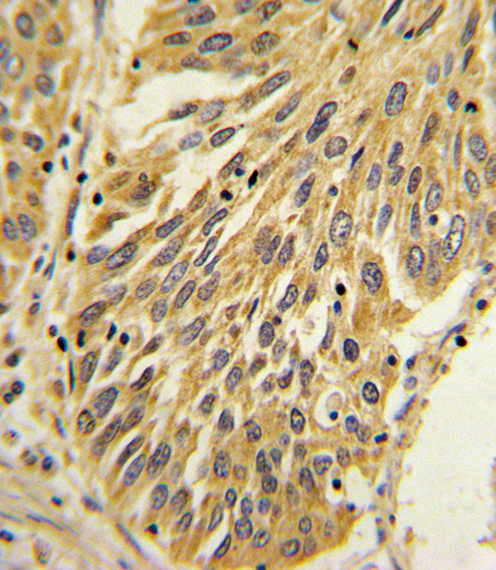

Formalin-fixed and paraffin-embedded human lung carcinoma with IL1B Antibody (Center), which was peroxidase-conjugated to the secondary antibody, followed by DAB staining. This data demonstrates the use of this antibody for immunohistochemistry; clinical relevance has not been evaluated. |